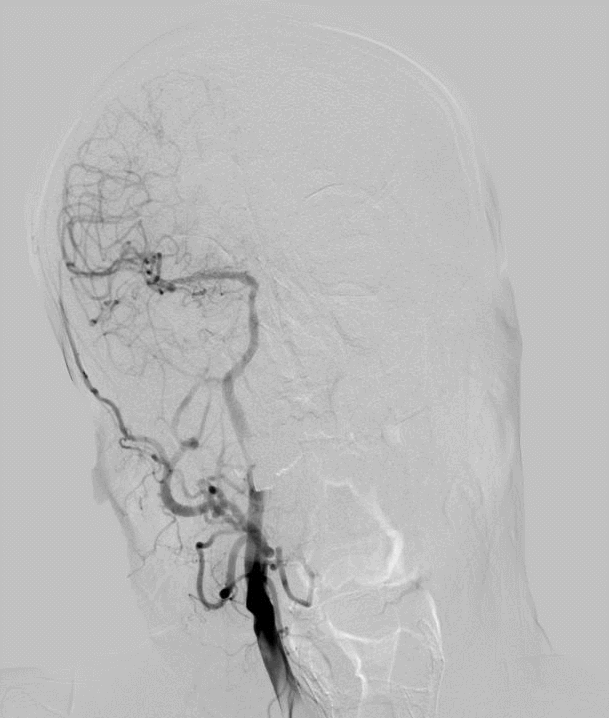

术前DSA

什么叫桡鞘【例久弥新】寻道于桡——瑞康通5.5F Introsky X导管鞘经桡取栓一例_https://www.jmylbn.com_新闻资讯_第8张

什么叫桡鞘【例久弥新】寻道于桡——瑞康通5.5F Introsky X导管鞘经桡取栓一例_https://www.jmylbn.com_新闻资讯_第9张

什么叫桡鞘【例久弥新】寻道于桡——瑞康通5.5F Introsky X导管鞘经桡取栓一例_https://www.jmylbn.com_新闻资讯_第10张

什么叫桡鞘【例久弥新】寻道于桡——瑞康通5.5F Introsky X导管鞘经桡取栓一例_https://www.jmylbn.com_新闻资讯_第11张

什么叫桡鞘【例久弥新】寻道于桡——瑞康通5.5F Introsky X导管鞘经桡取栓一例_https://www.jmylbn.com_新闻资讯_第12张